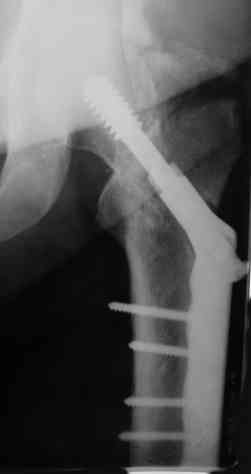

Вальгизирующая остеотомия по Marti с латерализацией, фиксация клинковой

пластиной (см. рис.) - хотя результат менее предсказуем, чем при эндпротезировании.

Поэтому отбрасывая все остальное, считаем, что Intertrochanteric valgus osteotomy или Межвертельная вальгусная остеотомия создает те необходимые биомеханические преимущества, которые восстановят измененную биомеханику.

Среди всех остальных этот вариант является менее инвазивным, отличный результат от 75-90%, отсутствует дополнительный риск повреждения кровоснабжения головки бедра, и главное - биомеханические преимущества.

Основной задачей является изменение механики из варуса в вальгус и установка вектора сил перпендикулярно к линии ложного сустава. При восстановлении необходимо учесть, что чрезмерная вальгизация также является нежелательной. Увеличивается сила давления на сустав и на хрящ, что может привести к артрозным изменениям.

Технически все делается внесуставно, без вскрытия места ложного сустава, в положение больного на спине, для облегчения работы ближе к краю операционного стола.

На вертеле делается "срез" в латеральном кортекса для клинка пластины и специальное долото вводится под 90-градусным углом к бедру по заранее приготовленному предоперационному плану.

Делается межвертельная остеотомия с удалением клина в 20-30 градусов в зависимости от шеечно-диафизарного угла, а все остальное сделает 120 градусная Blade Plate.

Для предупреждения вальгуса механической оси конечности необходима латеризация бедра, кусок кости от остеотомии, уложеный между пластиной и латеральным кортексом, латерализует бедренный диафиз.

На представленных снимках некоторые моменты, предоперационный план, латерализация, расчет длины, ориентир для введения и наборы.